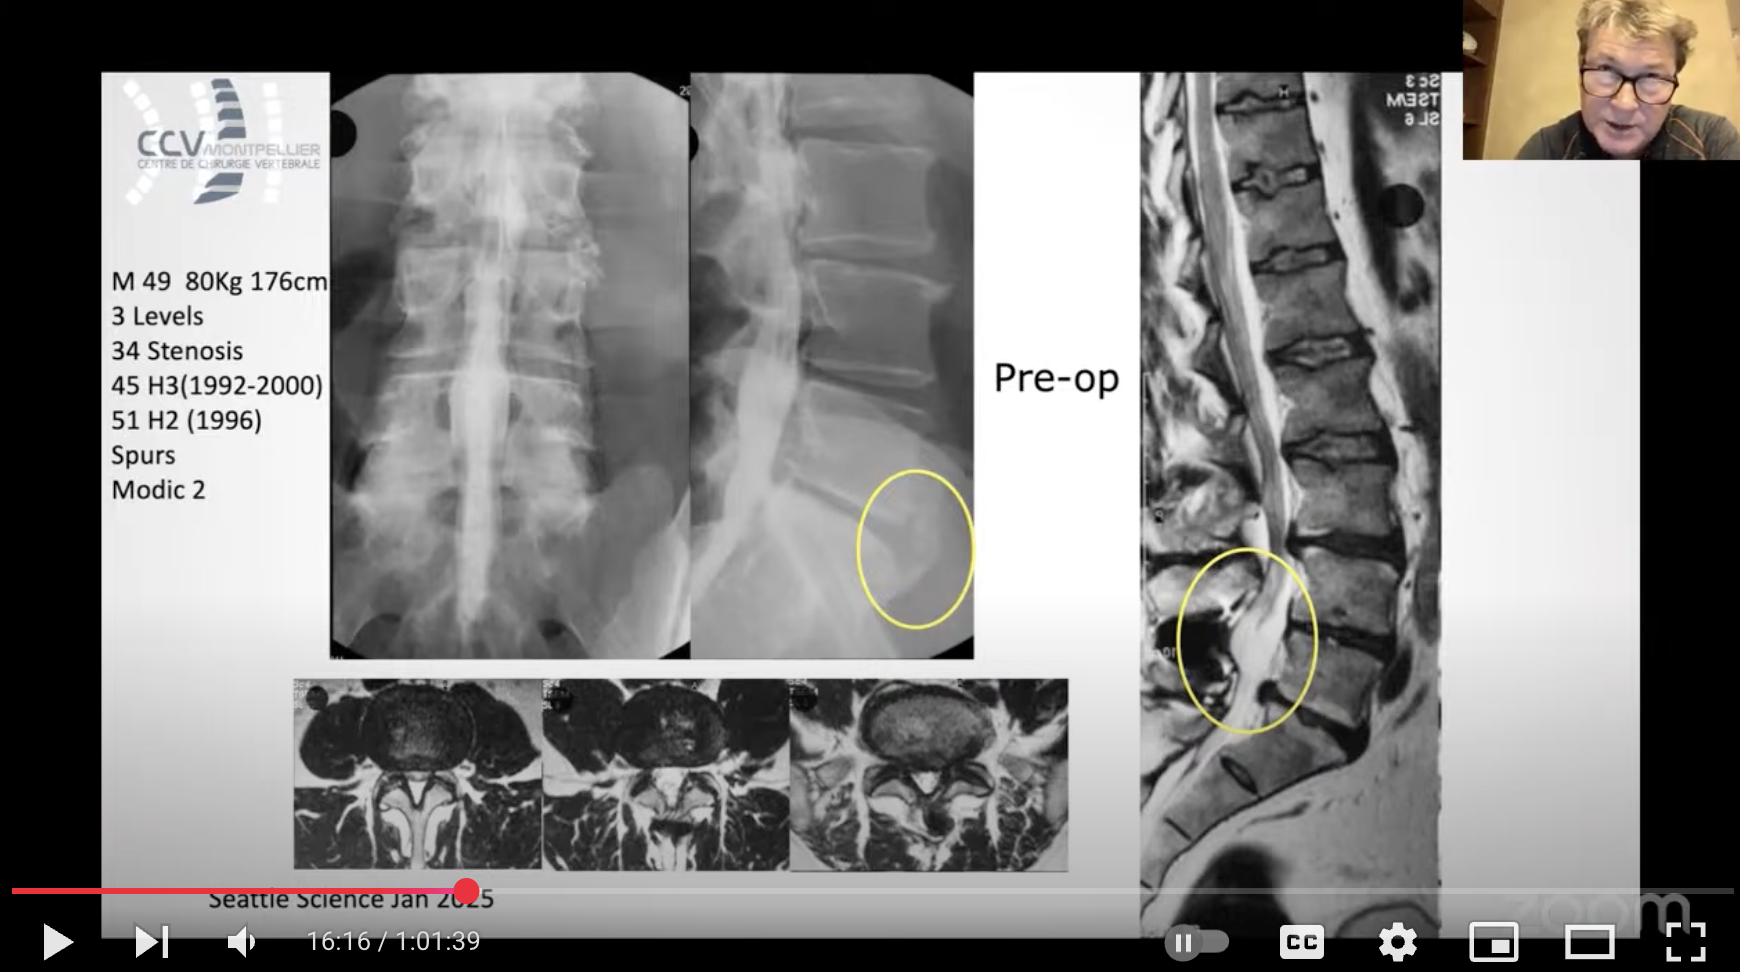

Spine Arthroplasty Case Discussion Series explores the real-world use of disc arthroplasty via case reviews with excellent as well as poor outcomes & complications. Experienced surgeons share cases that improve understanding of the expanding indications & complications of disc replacement surgery.